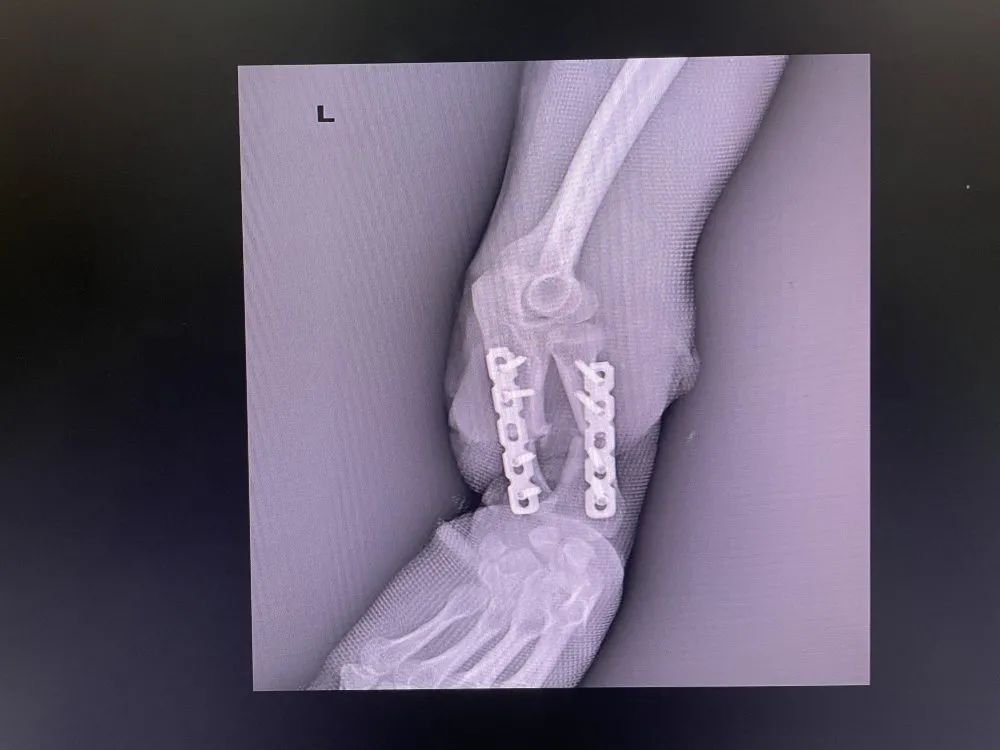

術后DR

1625448370477488.jpg

1625448370412535.jpg